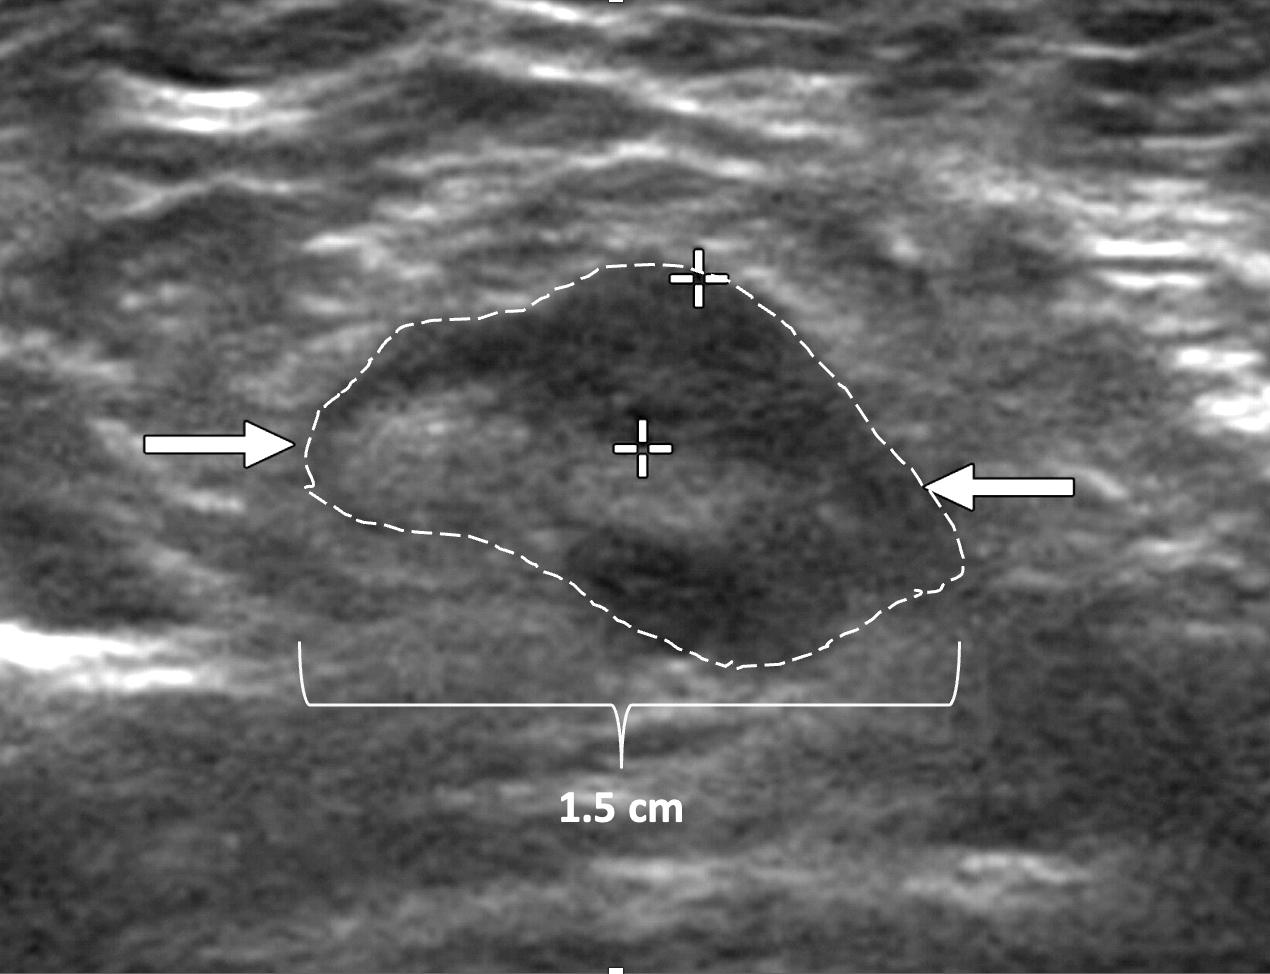

Ultrasound of the axilla. Axillary ultrasound permits detection of abnormal appearing lymph nodes that might not be detected on physical examination, mammography, or breast MRI. Axillary ultrasound is the most sensitive imaging study for detection of subtle changes in the shape or thickness of a lymph node cortex that might indicate the presence of lymph node metastasis (Image 3). Detection of suspicious lymph nodes determines clinical cancer stage and requires a specific plan to manage the possibility of lymph node metastasis.

Image 3. Hash marks outline abnormal appearing axillary lymph node measuring 1.5 cm in maximal diameter. Paired “+” marks indicate the span of a 0.4 cm area of focal cortical thickening that is suspicious for a metastatic deposit within the lymph node.